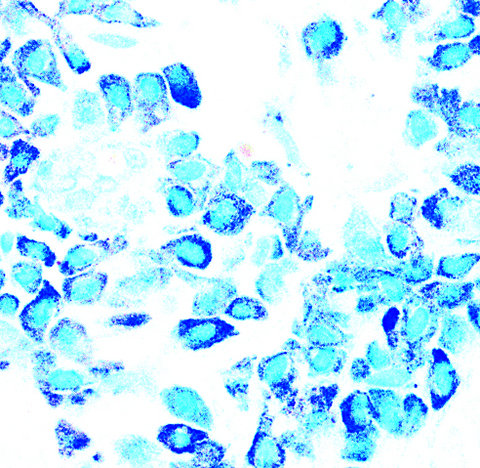

- Mast cells are round or spindle shaped with abundant eosinophilic cytoplasm, distinct cytoplasmic boundaries, large pale nuclei

Microscopic (histologic) images

Positive stains

- Toluidine blue and Giemsa demonstrate metachromasia (granules are purple red)

- Leder (chloroacetate esterase), CD117 / c-kit